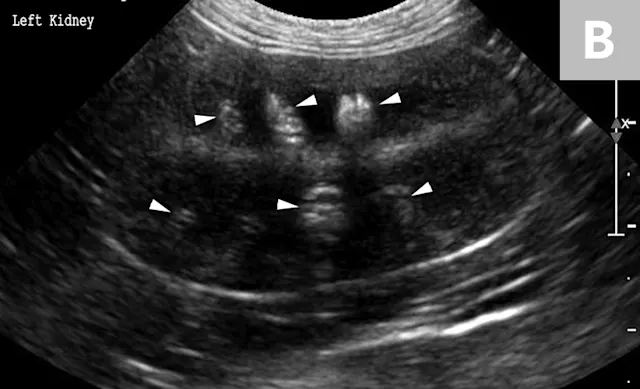

Renal calculi can vary markedly in size, number, shape, and opacity (Figure 3). Dystrophic mineralization of the renal parenchyma, often associated with the collecting system, is another differential for mineralization localized to the kidney (Figure 4). A combination of radiography, positive contrast radiography (excretory urography), and ultrasonography has been shown to have an increased sensitivity for the diagnosis of ureteral calculi when compared with ultrasonography alone (Figure 5).4

FIGURE 6A

Mild to moderate right hydronephrosis and proximal ureteral dilation in a Dalmatian.